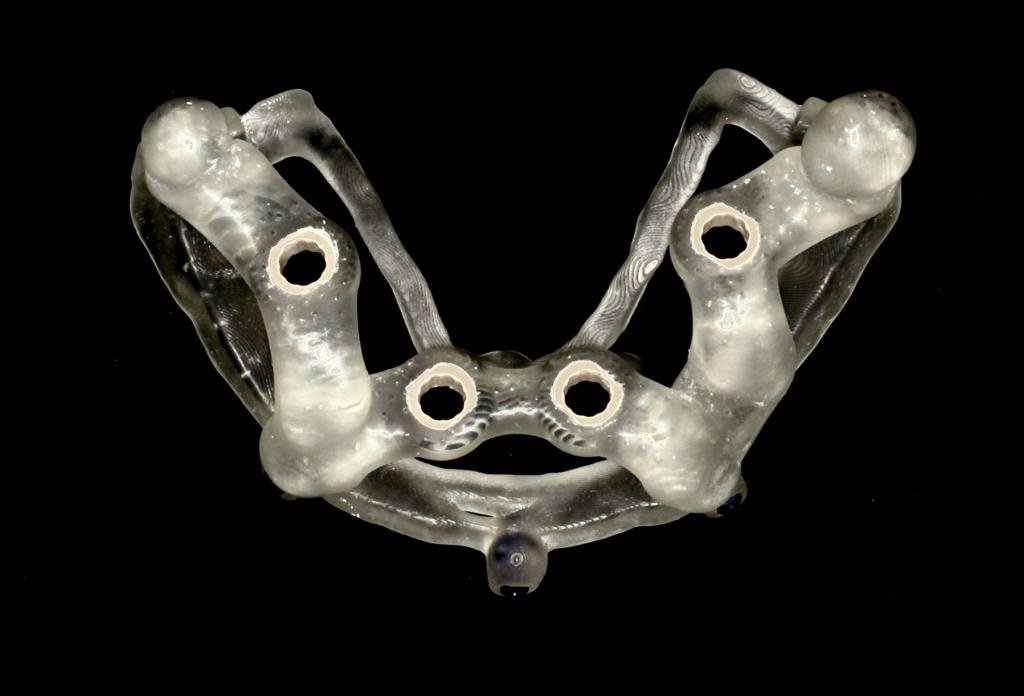

2. "All-on-X" Full-Arch Restoration

For patients who are missing most or all of their teeth in an arch, the All-on-X protocol (often All-on-4 or All-on-6) is a life-changing solution. Instead of one implant per tooth, we strategically place a specific number of implants (the "X") to support a full bridge of teeth.

B. Overdentures (Removable)

Sometimes called "Snap-on Smiles," this is a more affordable yet highly stable alternative to traditional dentures.

• How it works: The implants have specialized attachments (like snaps or a bar) that "clip" into the underside of the denture.

• Experience: It is removable for cleaning. While it provides much better stability than a standard denture (no slipping or adhesives), it is still a removable appliance.

• Benefit: Greatly improves chewing efficiency and confidence compared to traditional dentures.